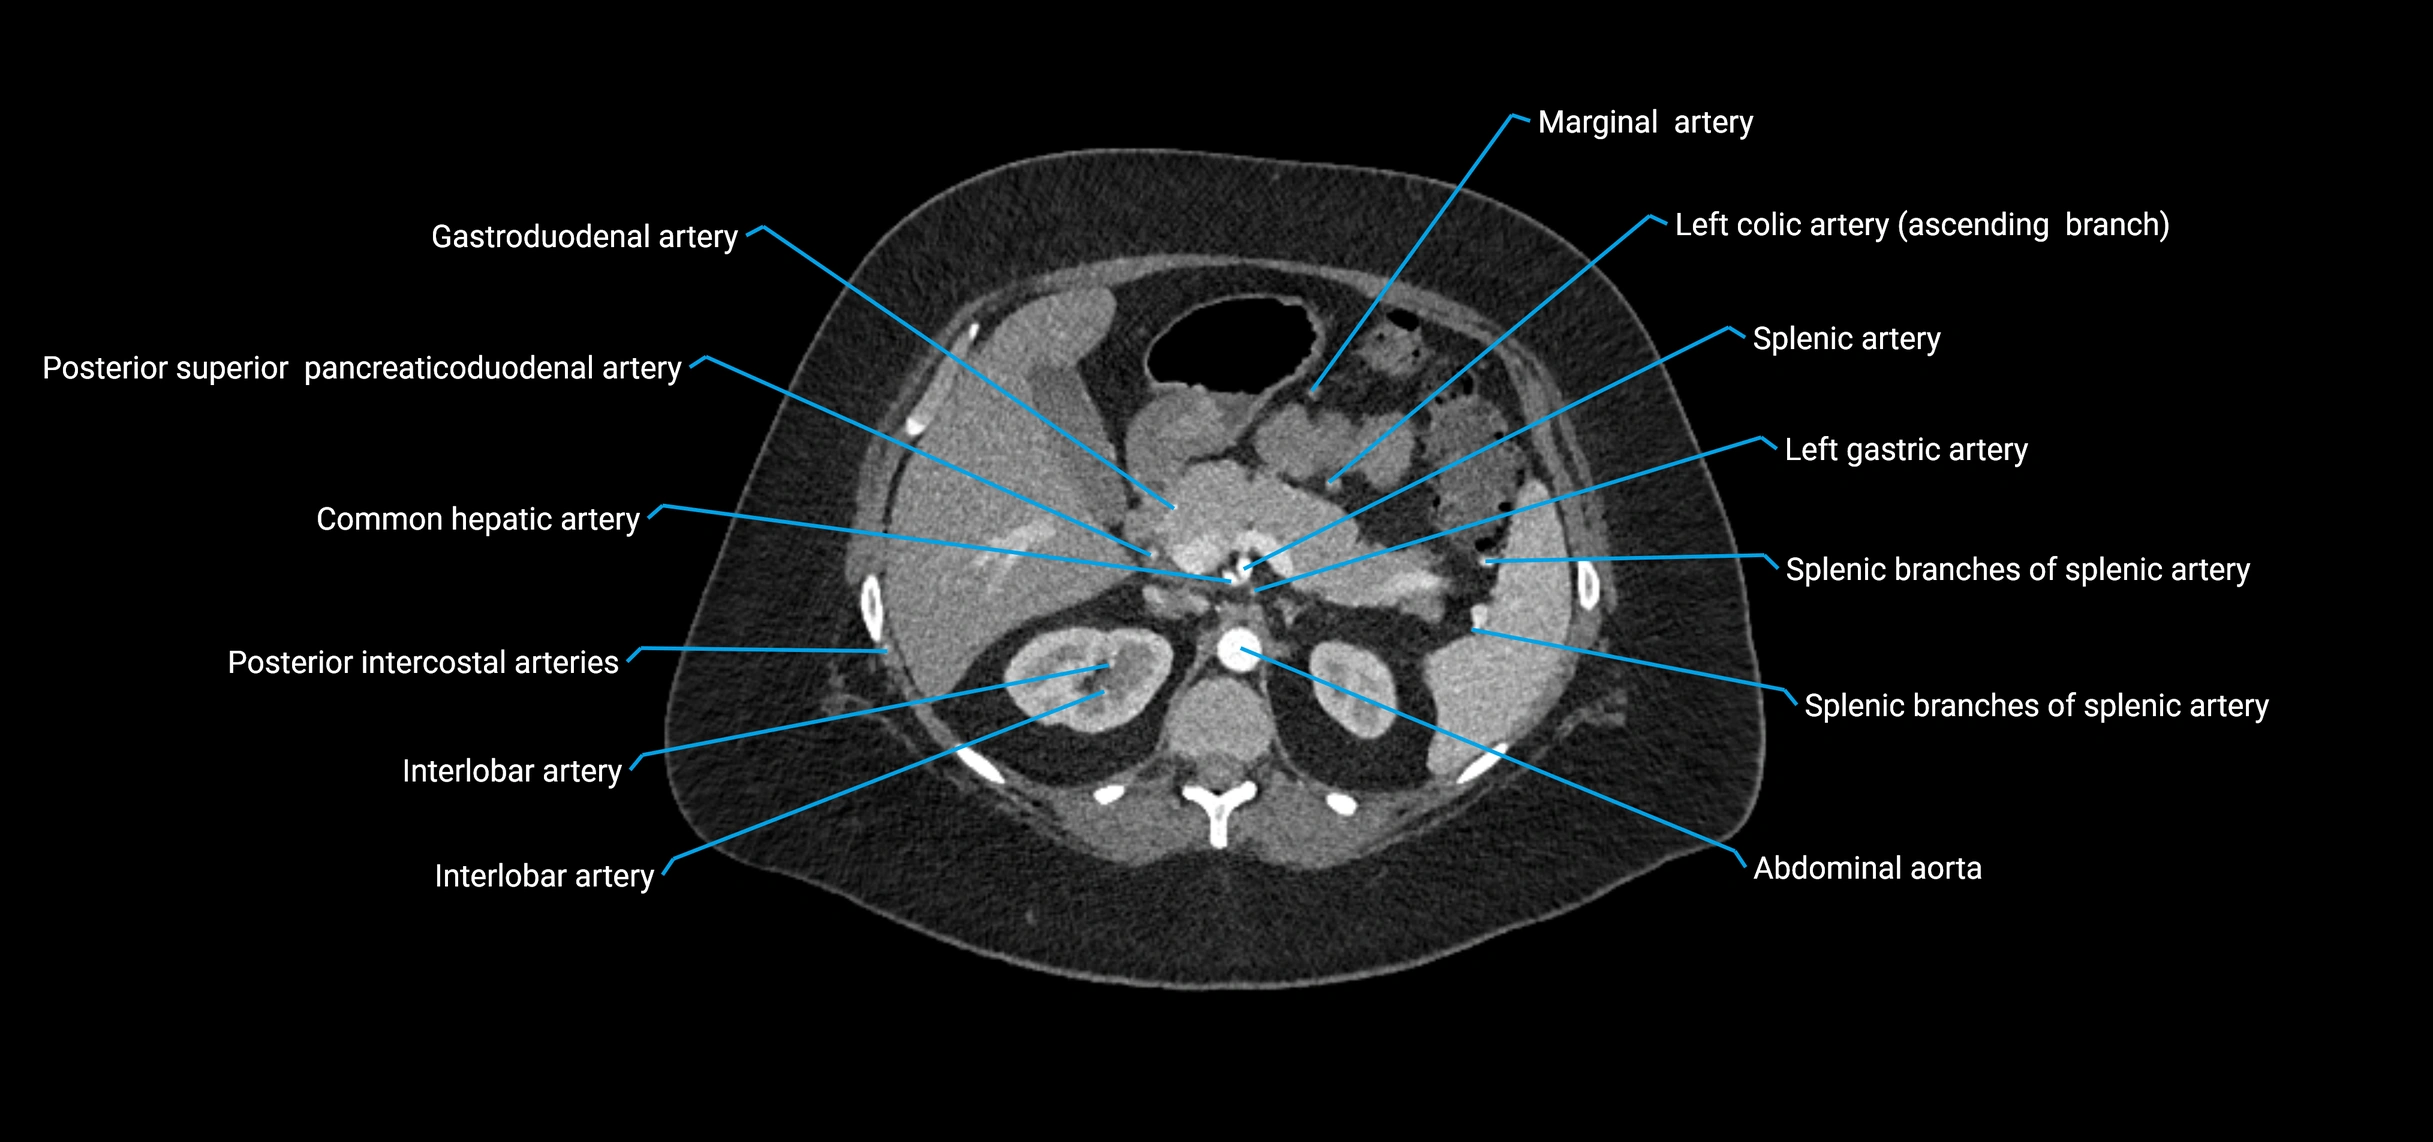

Contrast-enhanced CT (CTA):

• Gold standard for abdominal aortic imaging

• Provides excellent detail of lumen, wall, aneurysm, thrombus, and branch vessels

• Multiplanar and 3D reconstructions help in aneurysm measurement, stent graft planning, and dissection evaluation

• Unpaired visceral branches: celiac trunk, superior mesenteric artery (SMA), inferior mesenteric artery (IMA)

• Paired visceral branches: middle suprarenal arteries, renal arteries, gonadal arteries (testicular or ovarian)